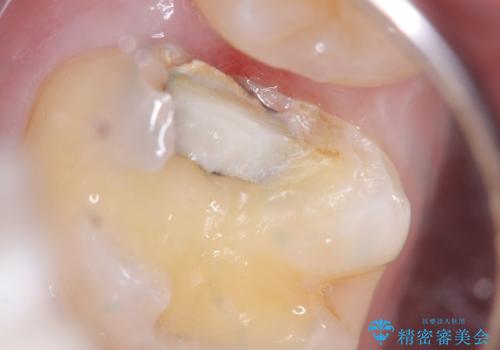

おそらくCAD/CAMインレーと思われる補綴物と歯質の不適合による二次う蝕でした。また、インレーを除去したところ、側室底面の歯質の上に裏層材が一部乗っており、歯質マージンとなっていなかったこともリークの一つの原因と考えられます。

適合性、審美性、材料安定性からセラミックインレーでのやり替えとなりました。う蝕を除去いていくと、残存歯質が薄く破折リスクの高い部位が出てきたため患者さんにも説明し、アンレー窩洞としました。